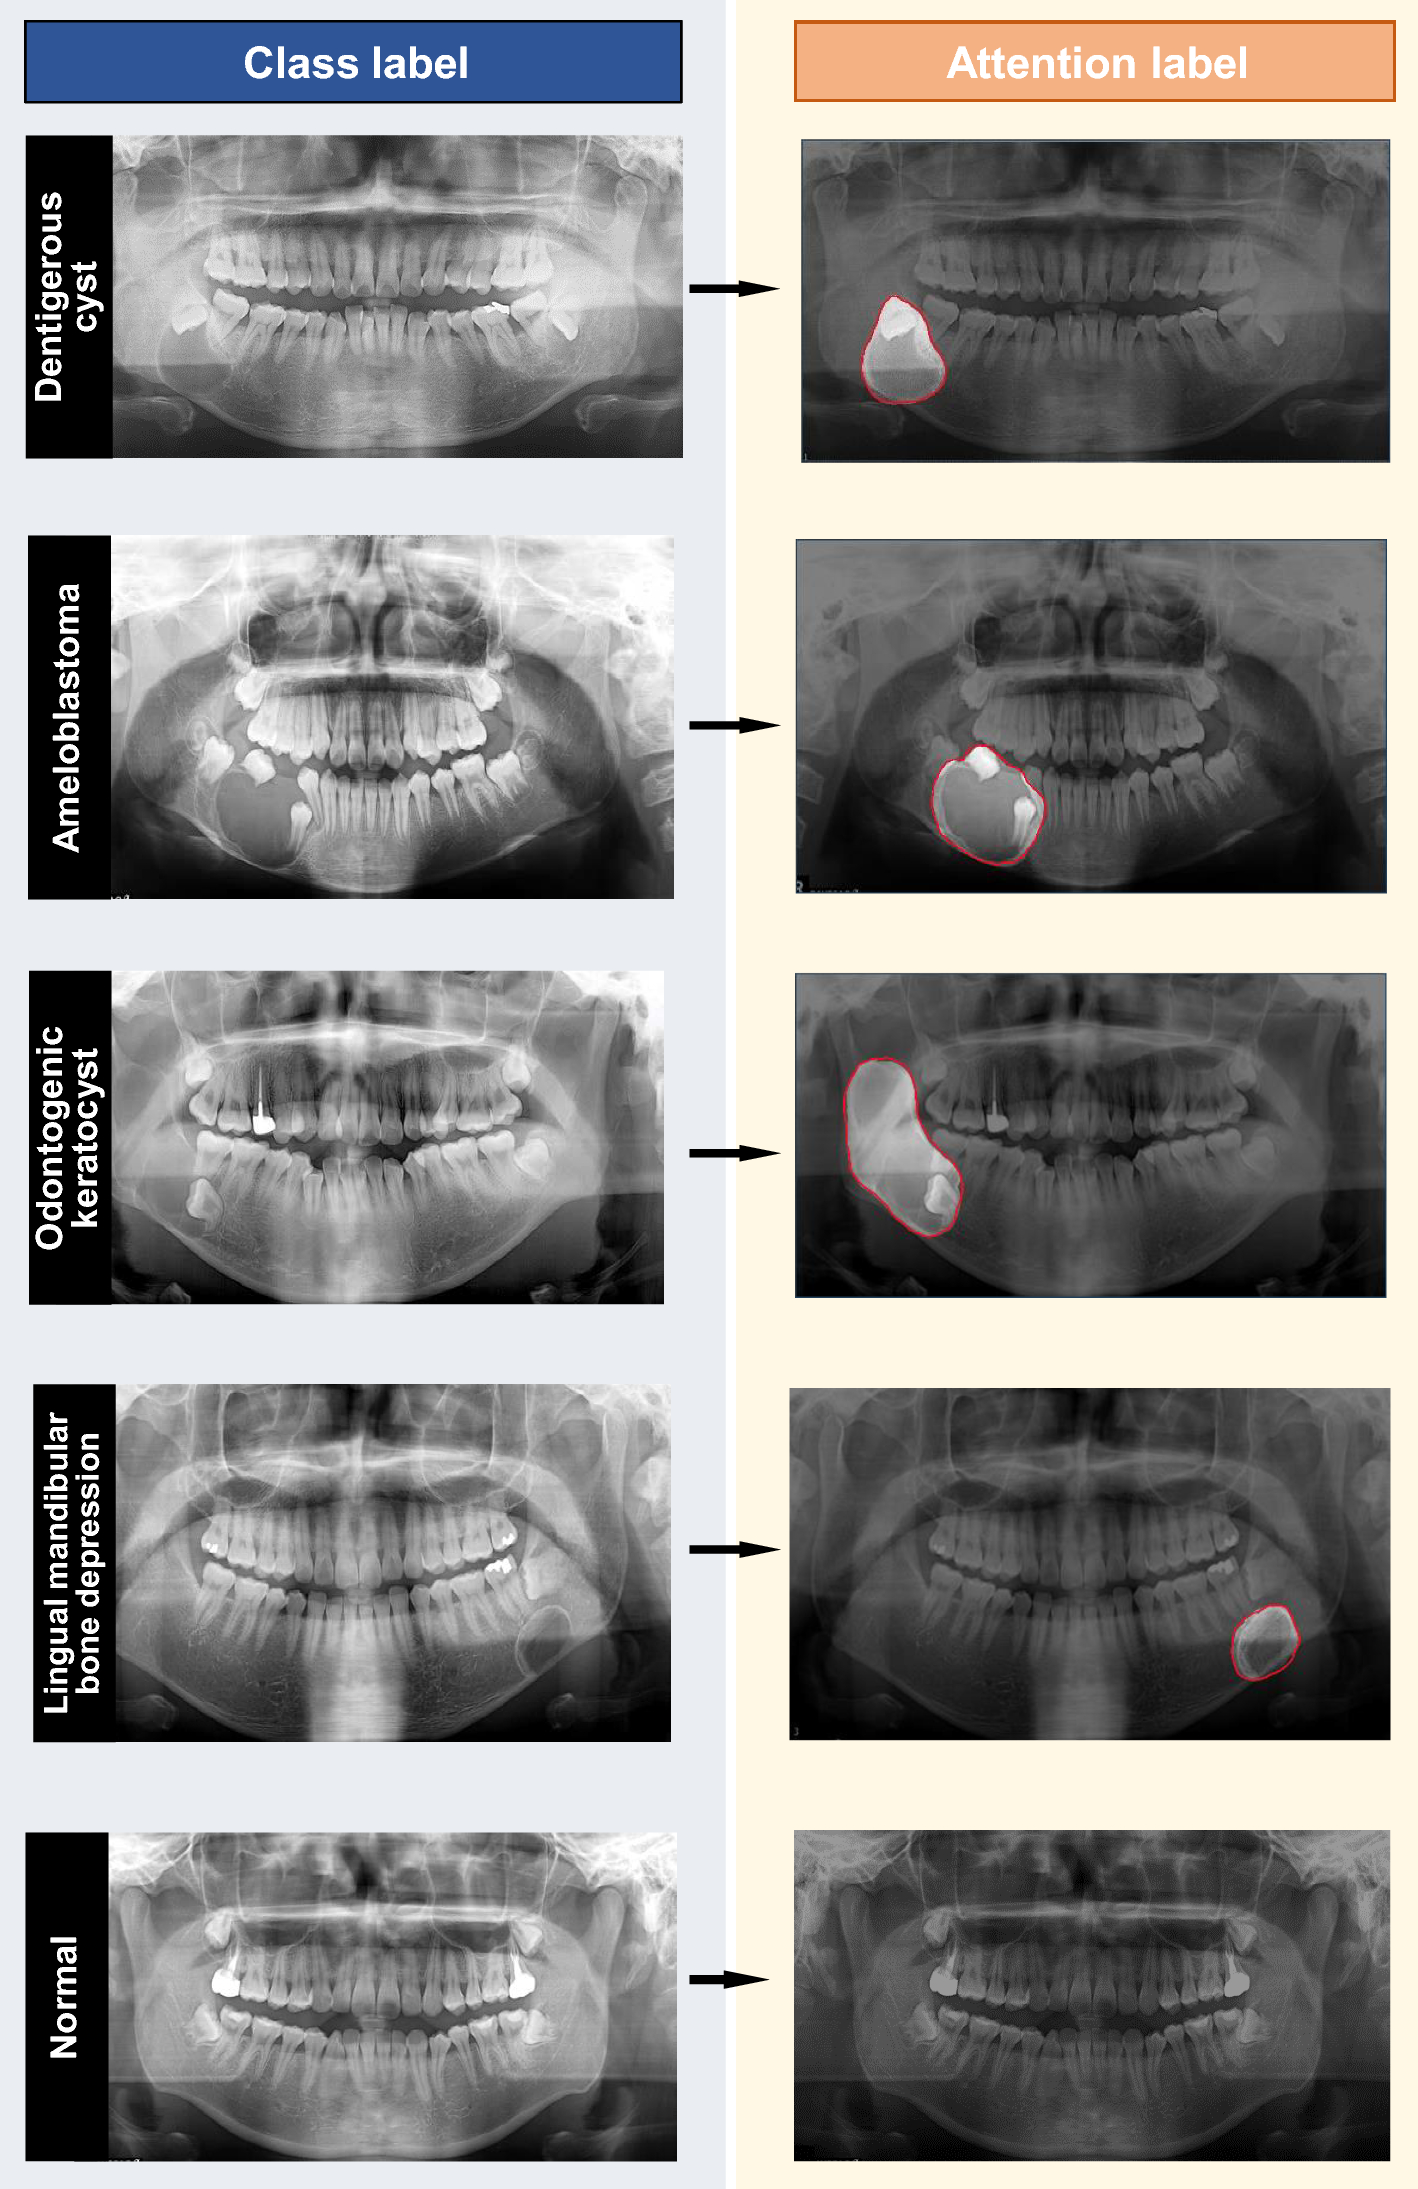

Data class label and attention label using box and border-specific annotation.

From: Attention-guided jaw bone lesion diagnosis in panoramic radiography using minimal labeling effort